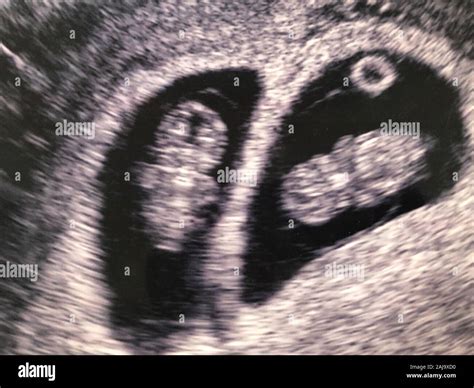

Ultrasound 9 Weeks Twins

Embarking on the journey of parenthood is an exciting and transformative experience, especially when expecting twins. One of the most crucial milestones in this journey is the Ultrasound 9 Weeks Twins scan. This early ultrasound provides invaluable insights into the development and health of the twins, offering parents a glimpse into their babies' world. Understanding what to expect during this ultrasound can help alleviate anxieties and prepare parents for the road ahead.

The Ultrasound 9 Weeks Twins scan is typically performed between 8 and 10 weeks of pregnancy. At this stage, the embryos are still very small, but significant developments are occurring. The primary goal of this ultrasound is to confirm the presence of two gestational sacs, each containing an embryo. This confirmation is crucial for determining the type of twin pregnancy—whether it is dizygotic (fraternal) or monozygotic (identical).